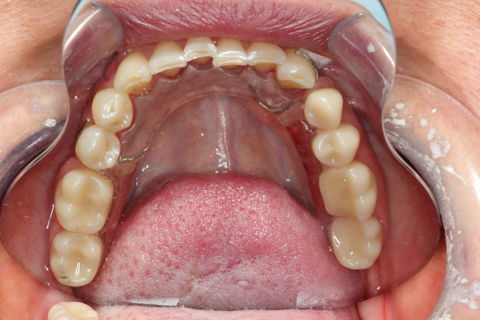

PPR Provisória Inferior

Paciente chegou no consultório relatando incomodo no elemnto 13, ao executar os exames clínicos e radiográficos constatou-se uma trinca na raiz, gerando a mobilidade e instabilidade da coroa e do pino metálico, foi então feita a exodontia do mesmo. Também constatou-se mobilidae acentuada no elemento 35 necessitando também da exodontia. Foi feita 2 PPR´s provísorias, uma superior e uma inferior, pois a paciente já apresentava PPR´s ao início do tratamento e essas após a exo não apresentam retenção.Segue imagem das PPR´s provisórias, esperando a correta cicatrização e adequação do meio bem como restaurações necessárias, para confecção das próteses definitivas.